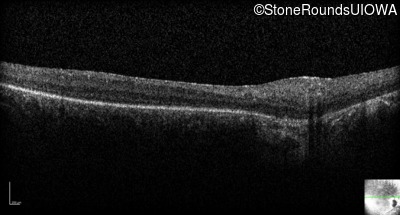

Age at visit:

28 years

OD

OS

Light Perception

OCT Stack

SECORD

RPGRIP1

His631Arg CAC>CGC

Pro237 del1ccA

AR